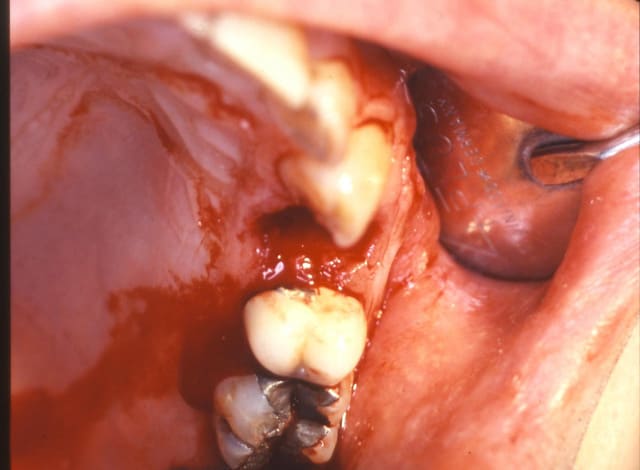

-fracture 25

-infection

-extraction (oups la ccm sur implant s'est descellée...)

-pas de pose d'implant car destruction de la paroi vestibulaire sur près de 5 mm

-pas de lambeau mais décollement vestibulaire muco-périosté à travers l'alvéole d'extraction et interposition d'une membrane de Collagen AT entre l'os et le périoste

-comblement BioOs et recouvrement avec même type de membrane

-conjonctif pédiculé tracté (comme j'ai pu) pour fermeture du site d'"extraction.